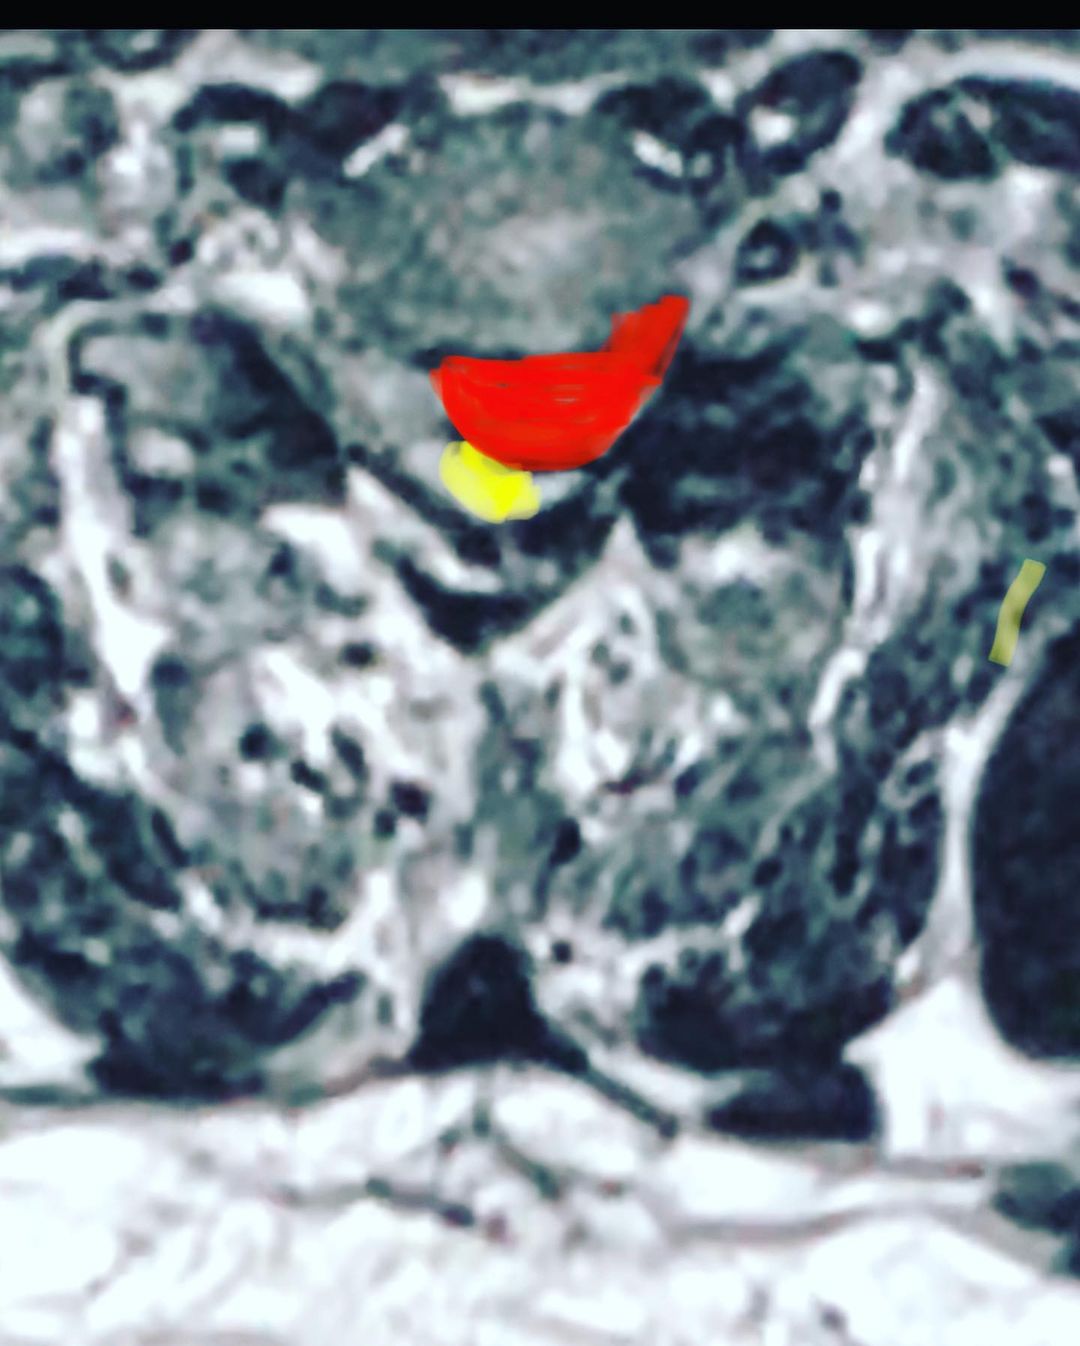

Hernia de disco

Ciática